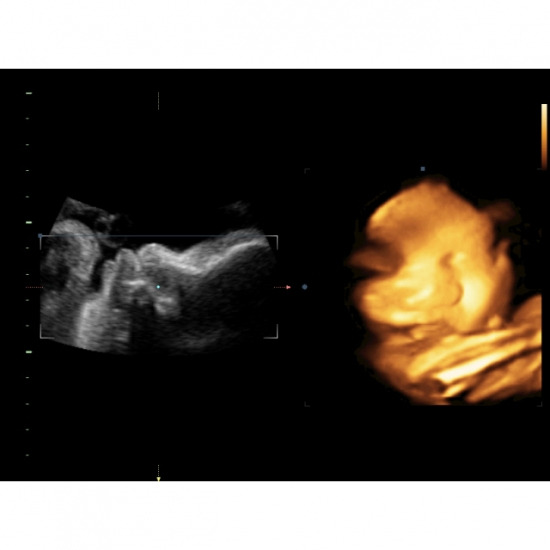

พระยาสุเรนทร์คลินิกเวชกรรม สาขาแกรนด์ออคิด บริการอัลตร้าซาวด์ 4 มิติ

อัลตร้าซาวด์ 4 มิติ สำหรับ อายุครรภ์เริ่มต้นที่ 28 สัปดาห์ ไม่เกิน 32 สัปดาห์